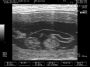

חדשות מרגשות יש הערב. לפני מספר דקות בלבד סיימנו את סריקת האולטרא סאונד של מארם,שהיום עומדת על יום 30 להריון מההרבעה הראשונה. מארם שכבר מראה סימנים חיצוניים היתה ברורה שבעלת שגר גדול, על אף שבסריקה הקודמת ניתן היה לאתר רק 6 עוברים בתוך קפלי המעי, היום ניתן היה לראות בבירור מושלם 9 גורים בריאים, שלמים ובעלי דופק מרגש של 345 פעימות לדקה בממוצע.